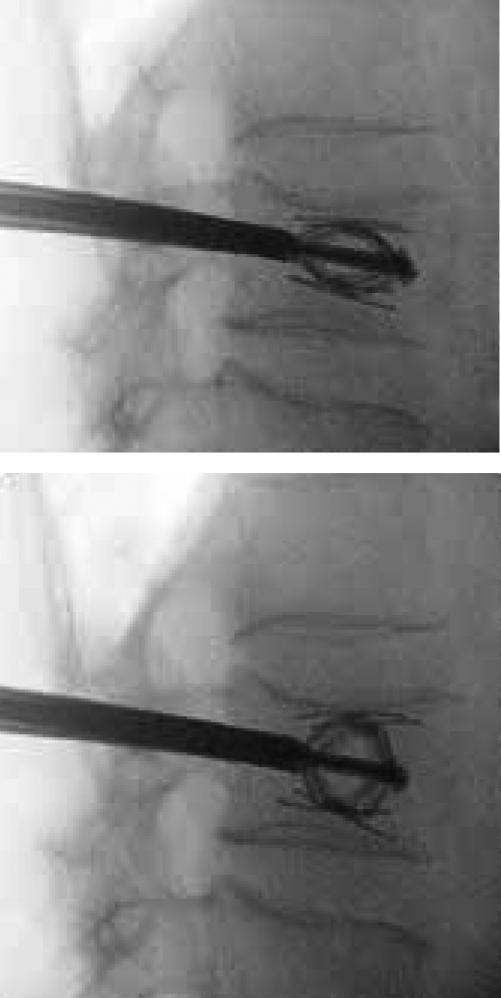

Der „SpineJack“ im Röntgenbild: Wie ein Wagenheber richtet das Implantat zusammengebrochene

Wirbelkörper wieder auf.